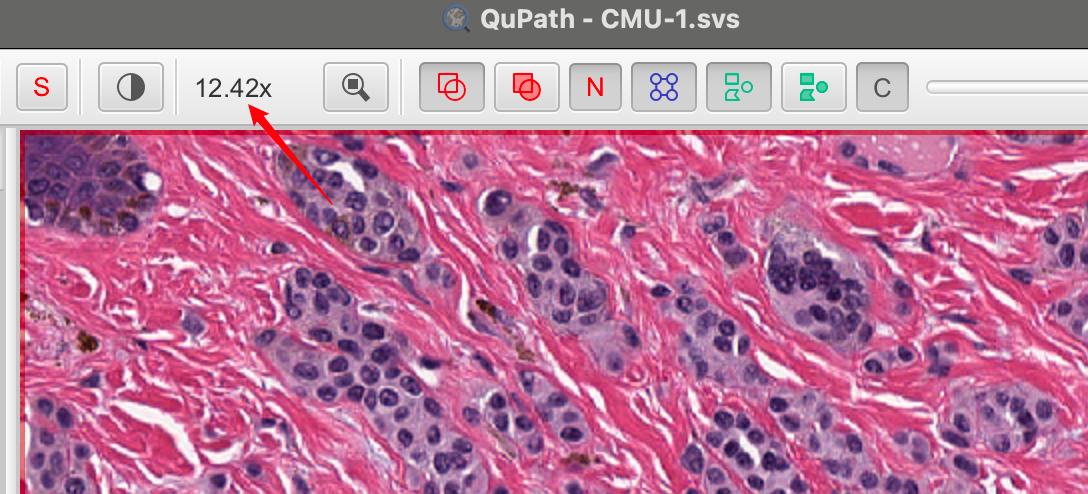

2-1:放大和缩小

要在 QuPath 中放大和缩小图像,请使用鼠标滚轮(或触控板上的等效滚动动作)。

如果您符合以下条件,也可以跳转到特定的放大倍数:

- 右键单击图像,然后选择其中一个缩放选项,例如“显示”‣“100%”,或

- 双击工具栏上的小放大倍数,然后在那里输入一个值。

2-2:平移

要在 QuPath 中平移大图像,首先确保在工具栏中选择了**“移动”**工具。然后单击图像上的任意位置,并按住鼠标按钮拖动鼠标进行移动。

或者,您可以点击右上角的概览图像自动跳转到特定区域。